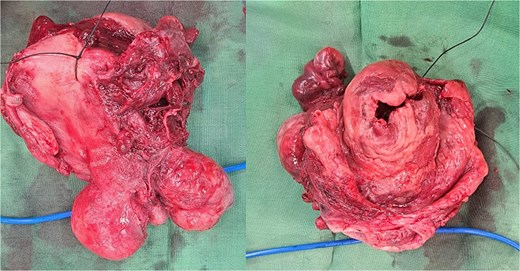

On examination, she was hypertensive and mildly tachycardic. No abdominal mass was identified. Her gynecology evaluation revealed a large pink mass with erosion and white plaque measuring around 30 × 10 × 8 cm (Fig. 1). No cervix-like structure or external uterine ostium was identified, but a point-like structure was identified on the apex, suspected to be the tubal opening. The mass consisted of a cystic and solid part. We suspected that it was a submucosal leiomyoma that had degenerated with cystic parts. Abdominal ultrasound revealed no uterus-like structure and visualized the bladder. The patient was diagnosed with NPUI and submucosal leiomyoma, and a hysterectomy was planned after stabilizing the blood sugar level.

Uterine inversion with submucosal leiomyoma on the corpus. The mass was found to be eroded and covered with slough. A point-like structure was identified at the apex of the mass, suspected of being the tubal ostium; however, the opening of the cervical canal was not identified.

Within the operation, a urinary catheter was inserted and the bladder location was identified. We pushed the mass cranially to reposition the uterus. During repositioning, the cyst mass was ruptured and released serous fluid, exposing the uterine cavity. Another team had started to do a laparotomy and performed a median incision. Intraabdominally, we found a vortex-like structure that had sucked the uterus outside, with a twisted round ligament. We decided to incise the cystic mass to decrease the uterus size, and a sondage was then inserted into the cavity to the cervix inside the abdomen. Then, we made a large bundle of gauze in the sondage handle. We decided to do a double approach to reposition the uterus. The sondage was pulled abdominally and pushed vaginally. Soon, the uterus was reversed, and hysterectomy was performed (Figs 2 and 3). The operation was without complication, with 300 cc of bleeding. Postoperatively, the patient had a good recovery. However, a week after discharge, the wound was not healing properly, with some serous fluid coming out of the wound. A superficial surgical site infection was suspected and managed accordingly, with joint care with internal medicine for her diabetes. The histopathological result was angiomatous leiomyoma submucosum, and no further evaluation was needed.

Submucous leiomyoma that was extracted from the uterus. It showed a cystic white degeneration with serous fluid inside.

The uterus with the cervix. The corpus was already dissected and excised from the submucous leiomyoma.